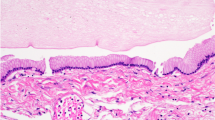

Complete removal of contrast-enhancing malignant gliomas can be difficult, and most neurosurgeons overestimate the degree of resection they are able to achieve [88, 89]. For this reason, technologies to improve extent of resection have been of interest. Neuro-navigation remains limited by registration constraints and brain shift throughout the course of the operation. Intraoperative ultrasound requires substantial experience to interpret the imaging. iMRI is expensive and available in only a number of specialized centers. 5-ALA is a nonfluorescent amino acid precursor that induces the accumulation of fluorescent porphyrins (mainly protoporphyrin IX) in malignant glioma. 5-ALA is produced in the mitochondria of all human cells, and under normal conditions 5-ALA and protoporphyrin IX are tightly controlled under a negative feedback loop [90]. However, exogenous 5-ALA leads to increased intracellular concentrations of fluorescent protoporphyrins in various malignant tumors, which peak 6 hours after administration and remains elevated for 12 hours [91–93]. Protoporphyrin IX has an absorption band strongest in the 380 ± 420 nm spectrum emitting red fluorescence at 635 nm and 704 nm in brain tissue [94]. 5-ALA induced fluorescence does not occur in healthy brain, and blood-brain barrier disruption in glioma allows the low lipid soluble 5-ALA to penetrate glioma tissue [93, 95].

5-ALA is administered either intravenously or orally 3 hours before the induction of general anesthesia with a goal of tumor removal 4–5 hours after 5-ALA administration [93]. A long-pass filter mounted to the surgical microscope allows for tumor visualization as the operator switches between white light and violet (Fig. 4).

5-ALA has been successfully used to better visualize malignant gliomas leading to improved extent of resection and longer patient survival. Microsurgical resections tailored for complete removal of all fluorescent material (“5-ALA complete resection”) offer greater 6-month and overall survival in malignant glioma without increase in postoperative neurologic deficits [93, 96, 97]. A phase III clinical trial conducted in Germany by the 5-ALA study group randomly assigned 322 patients with suspected malignant glioma to either conventional white light microsurgery or fluorescence-guided surgery assisted with 5-ALA. 5-ALA patients received 20 mg/kg of 5-ALA for a fluorescence-guided resection. After a mean follow-up of 35.4 months, 65 % of 5-ALA patients received complete removal of all contrast-enhancing tumor compared with 36 % of conventional white light microsurgery patients. 5-ALA patients experienced a 50 % improvement in 6-month progression-free survival (41 % vs 21.1 %) [97]. The literature provides class IIb evidence that 5-ALA-assisted extent of resection contributes to survival in glioblastoma [98]. 5-ALA is now combined with iMRI and direct cortical stimulation mapping to preserve eloquent functional pathways [99–101].